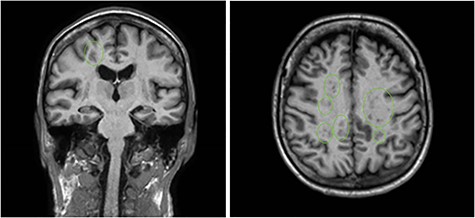

MRI brain demonstrating multifocal infarctions in both the anterior and posterior circulation, consistent with a cardioembolic source.

The patient was admitted for further investigation. MRI brain demonstrated multiple sites of ischaemic change in both the anterior and posterior circulation (Fig. 2). A cardiac embolic source was considered and TTE demonstrated a small hypoechoic focus 6 mm ×3 mm on the aortic annulus reported as representing either thrombus or atheroma. Further serological testing ruled out autoimmune and inflammatory conditions. A CT aortogram + coronary angiogram to exclude dissection or coronary artery disease given the rise in troponin noted an incidental pelvic mass (Fig. 3) thought to be arising from the adnexa. A confirmatory pelvic ultrasound reported a lesion arising from the right ovary with complex and vascular structure. CA 125 was >1500 (normal ref < 100). The patient was transferred to a tertiary centre with specialist onco-gynaecological and general surgical services for biopsy, which confirmed stage III high-grade serous ovarian cancer.

Case series reporting these principal mechanisms in stroke related to occult malignancy [5] have amalgamated diagnostic clues which point the clinician towards the diagnosis. These include elevated D-dimer, thrombocytopenia, thrombophilia or raised tumour markers [3–6]. In addition, diffusion-weighted imaging demonstrates a typical uniform multifocal ischaemic stroke that is widely distributed across vascular territories [7]. Our patient’s laboratory and imaging results further validated these observations having raised D-dimer, tumour markers, thrombocytopenia and characteristic imaging features supportive of NBTE.